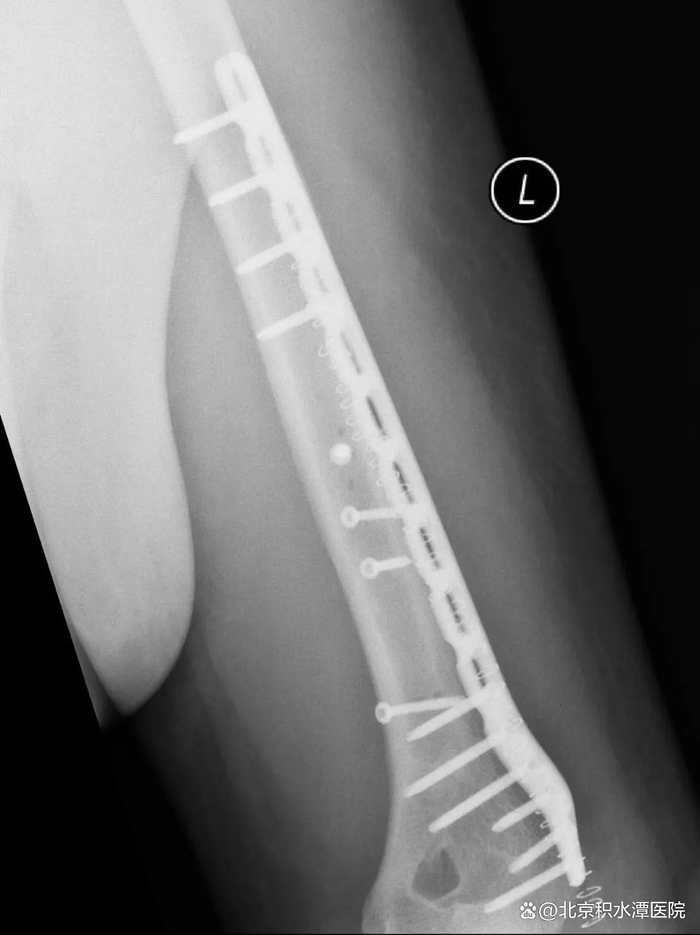

肱骨干骨折的治疗方法包括非手术治疗、闭合复位髓内钉内固定术和切开复位钢板螺钉内固定术等多种方式。采用非手术治疗时,可对患肢进行悬垂石膏固定或行闭合复位后使用上臂U型石膏固定,2-3周后解放肘关节,使用功能支具固定10-12周。由于扳手腕导致的肱骨干骨折几乎均为肱骨远端三分之一螺旋形骨折,闭合复位髓内钉内固定术不适合这类骨折,切开复位钢板螺钉内固定术是这类骨折的最佳的手术治疗方式

肱骨干骨折的治疗方式需要考虑患者的骨折类型、损伤程度、功能需求等多种因素,因此,患者应咨询专业骨科医生后决定具体治疗方式。